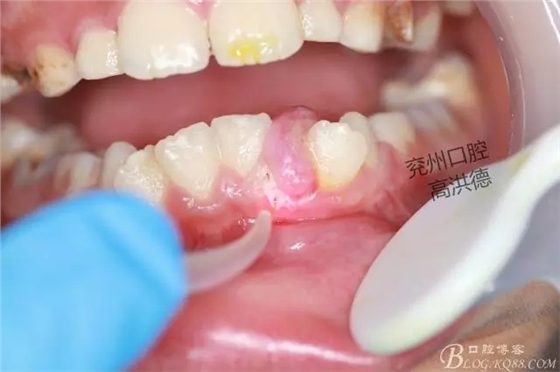

開始切除

繼續(xù)切除

口內(nèi)觀